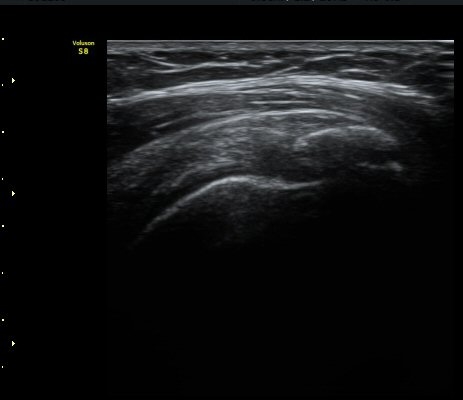

Áõ·Ê 2)

°ßºÀ¿À±¸µ¹±âÀδë Á¾´Ü¸é°Ë»ç¿¡¼­ ÀδëÀÇ ¿ÜÃø¿¡ ±¹¼ÒÀûÀÎ ÀÎ?ºñÈİ¡ °üÂûµÈ´Ù(»çÁø 3).

±Ø»ó°Ç Á¾´Ü¸é°Ë»ç½Ã ±Ø»ó°ÇÀÇ Ç¥Ãþ¿¡¼­ °üÂûµÇ´Â °ßºÀ¿À±¸µ¹±â Ⱦ´Ü¸é°Ë»ç»ó¿¡¼­

ÀδëÀÇ ºñÈİ¡ °üÂûµÈ´Ù(»çÁø 4). ±Ø»ê°ÇÀÇ Á¾´Ü¸é°Ë»ç¿Í Ⱦ´Ü¸é°Ë»ç¿¡¼­ ±Ø»ê°Ç ½ÉÃþ¿¡

Àú¿¡ÄÚ º´º¯ÀÌ °üÂûµÈ´Ù(»çÁø 5, 6).